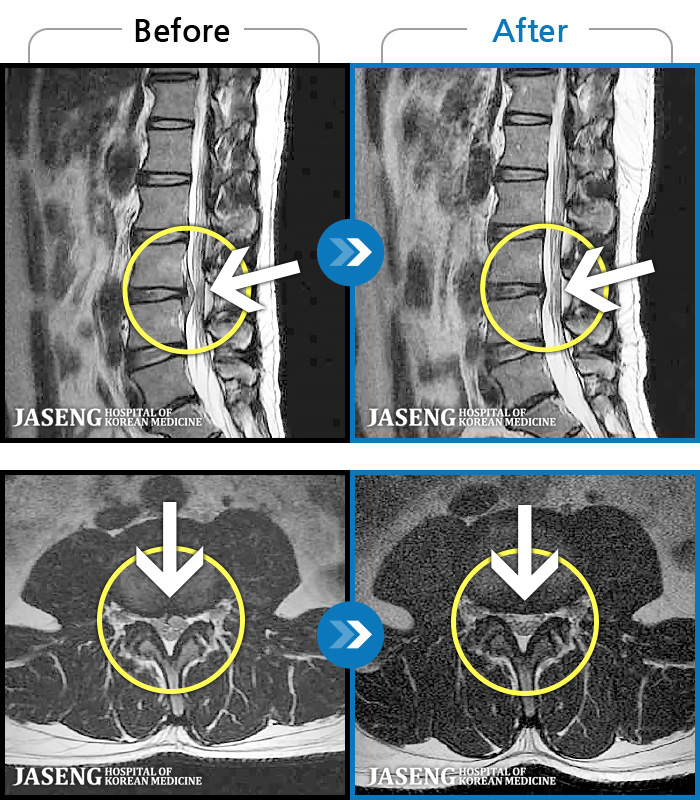

- MRI ġ

MRI ġ

1,240 MRI ũ ʸ Ȯϼ.